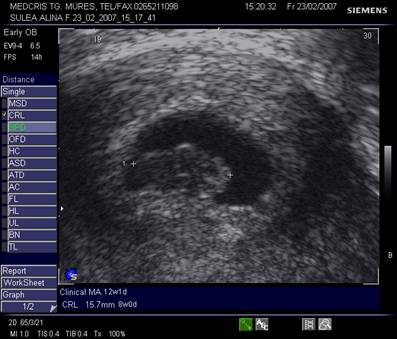

Fig nr.83 Discrepanta dintre lungimea cranio caudala embrionara (CRL intre calipere) ce corespunde la 8 saptamani si amenoreea de 12 saptamani, se remarca absenta veziculei viteline

Fig nr. 84. Discrepanta intre CRL (crown rump lenght sau lungimea craniocaudala)

si amenoree, la o sarcina oprita in evolutie